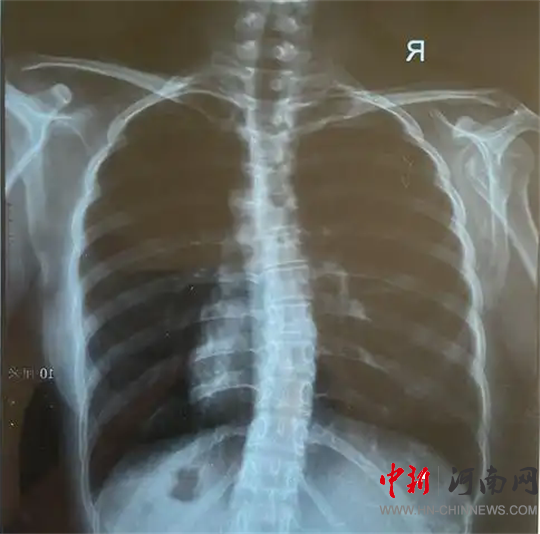

檢查結(jié)果為

脊柱側(cè)彎!

脊柱側(cè)彎,又稱脊柱側(cè)凸,是指脊柱偏離正中位置,身體向一側(cè)彎曲的骨骼畸形。

脊柱側(cè)彎絕大部分發(fā)生在青少年時期,是嚴(yán)重危及青少年群體身心健康的常見疾病,具有發(fā)病率高、起病隱匿等特點,發(fā)病高峰集中在10-14歲。